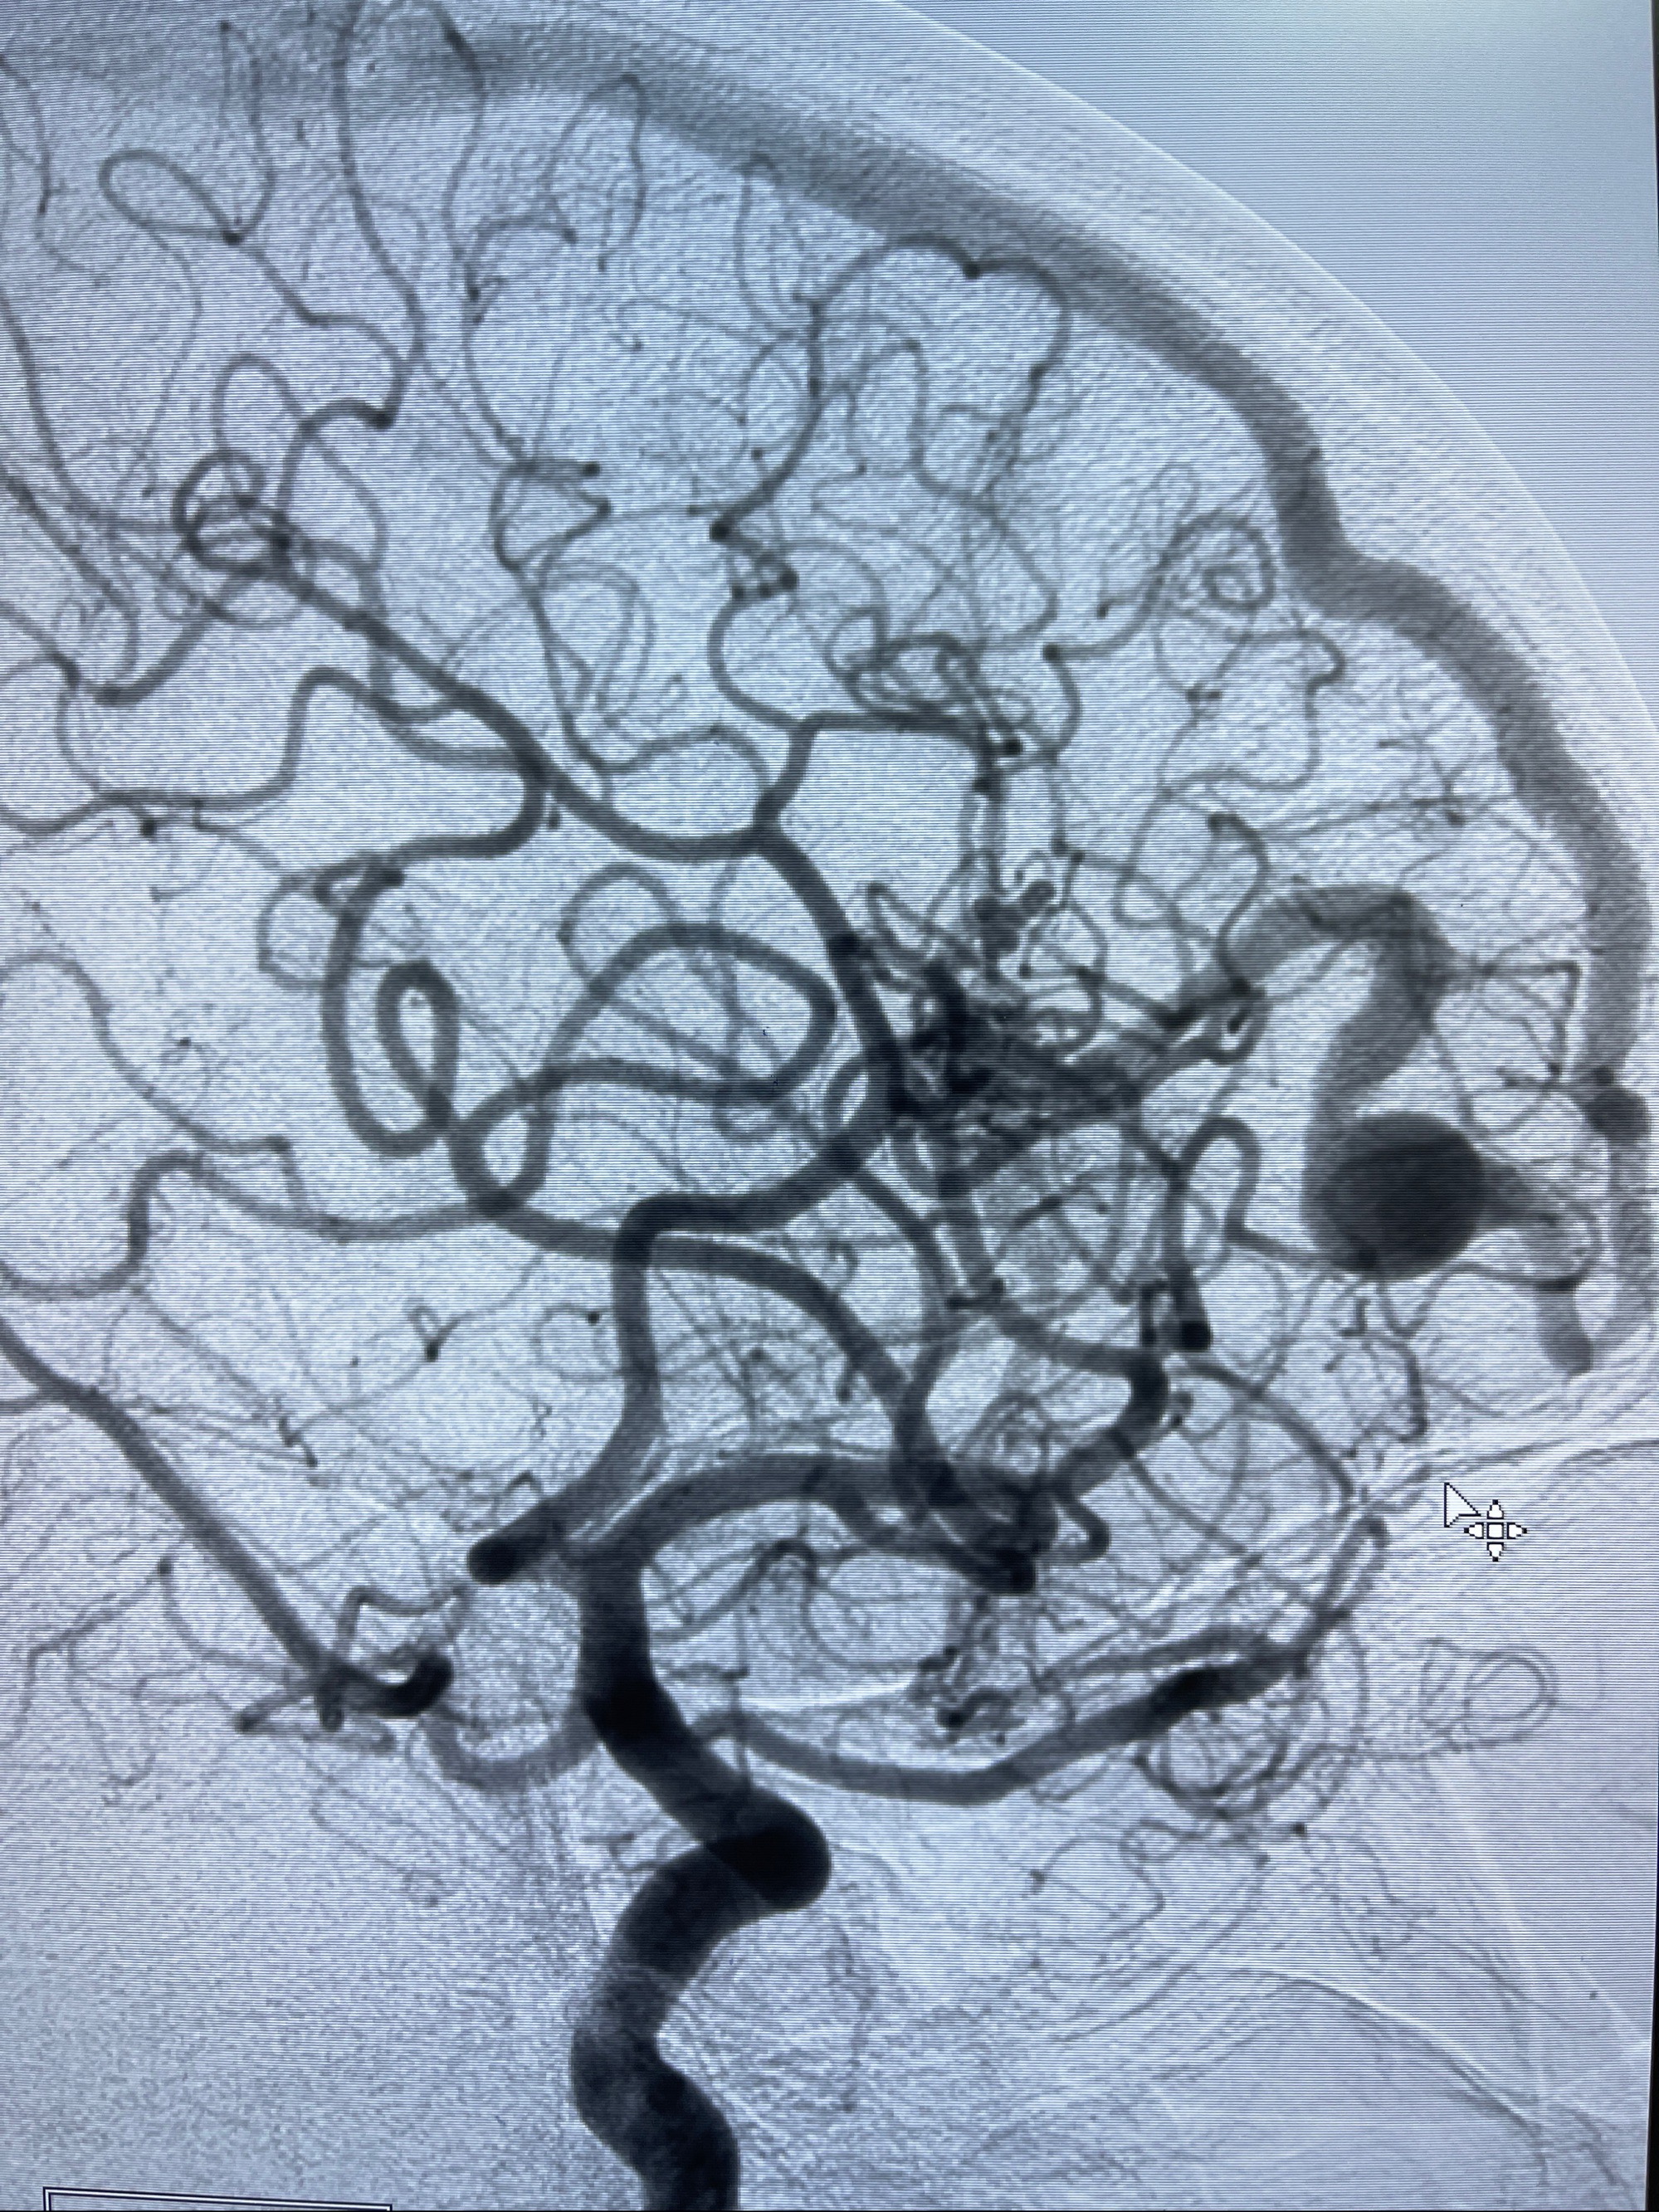

2023年8月21日]景德镇市第一人民医院脑血管造影检查,提示:主动脉弓、双侧颈总动脉、锁骨下动脉造影未见异常,左侧大脑前动脉静脉瘘。

2023-09-13全脑血管造影:前颅底硬脑膜动静脉瘘,供血动脉为双侧胼周动脉、眼动脉脑膜支,静脉向上矢状窦方向引流